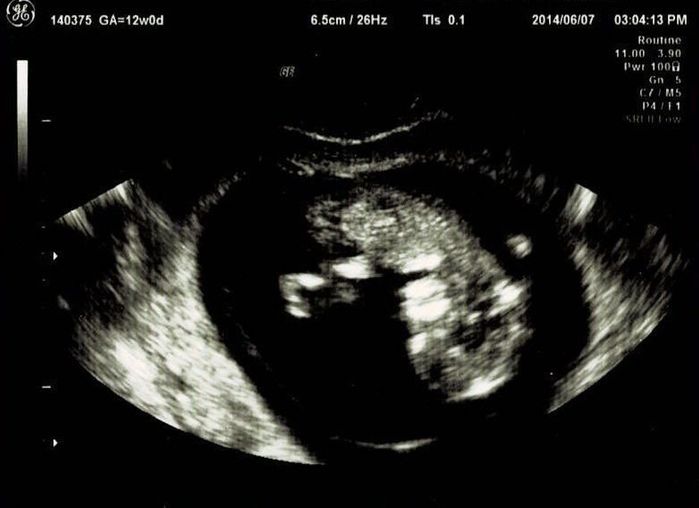

妊娠12週目エコー写真

つわり真っ盛り。しかし、おなかはまだ大きくありません。この日は採血をして、麻疹、風疹などの抗体があるか、梅毒の反応がないかなどの妊娠前期検査をしてもらいました。赤ちゃんはきちんと手足が見えて驚きました。さらには背骨まで確認できました。改めておなかの中に人間がいるという感慨がわいて、不思議な気持ちに。ガイコツみたいなエコーでもかわいいと感じました。